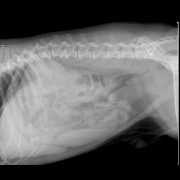

Uit de diepte wordt het probleem boven water gehaald,

de grasaar van het kruipertje